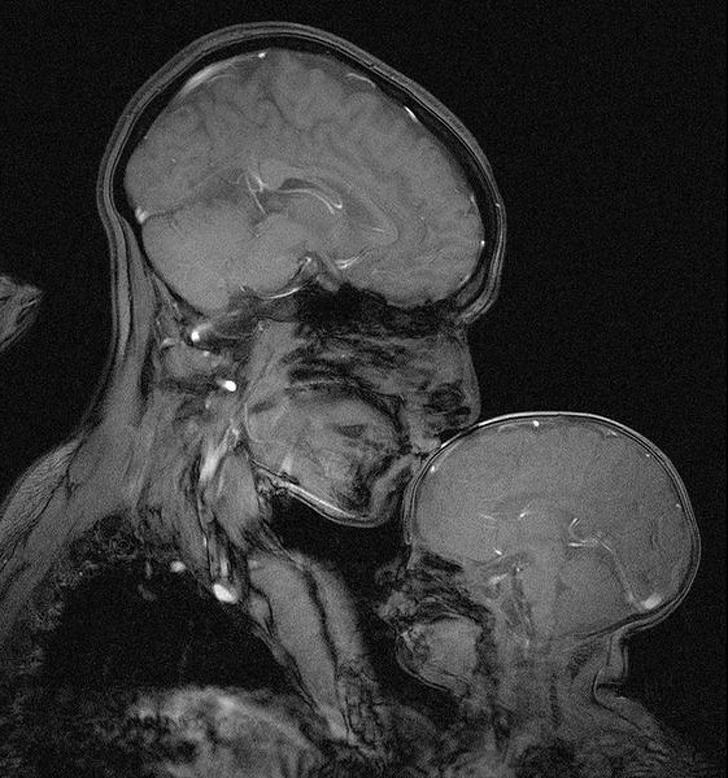

#1. The teeth of a person who is 7 (the photo on top) and a person who is 30 (the photo on the bottom)